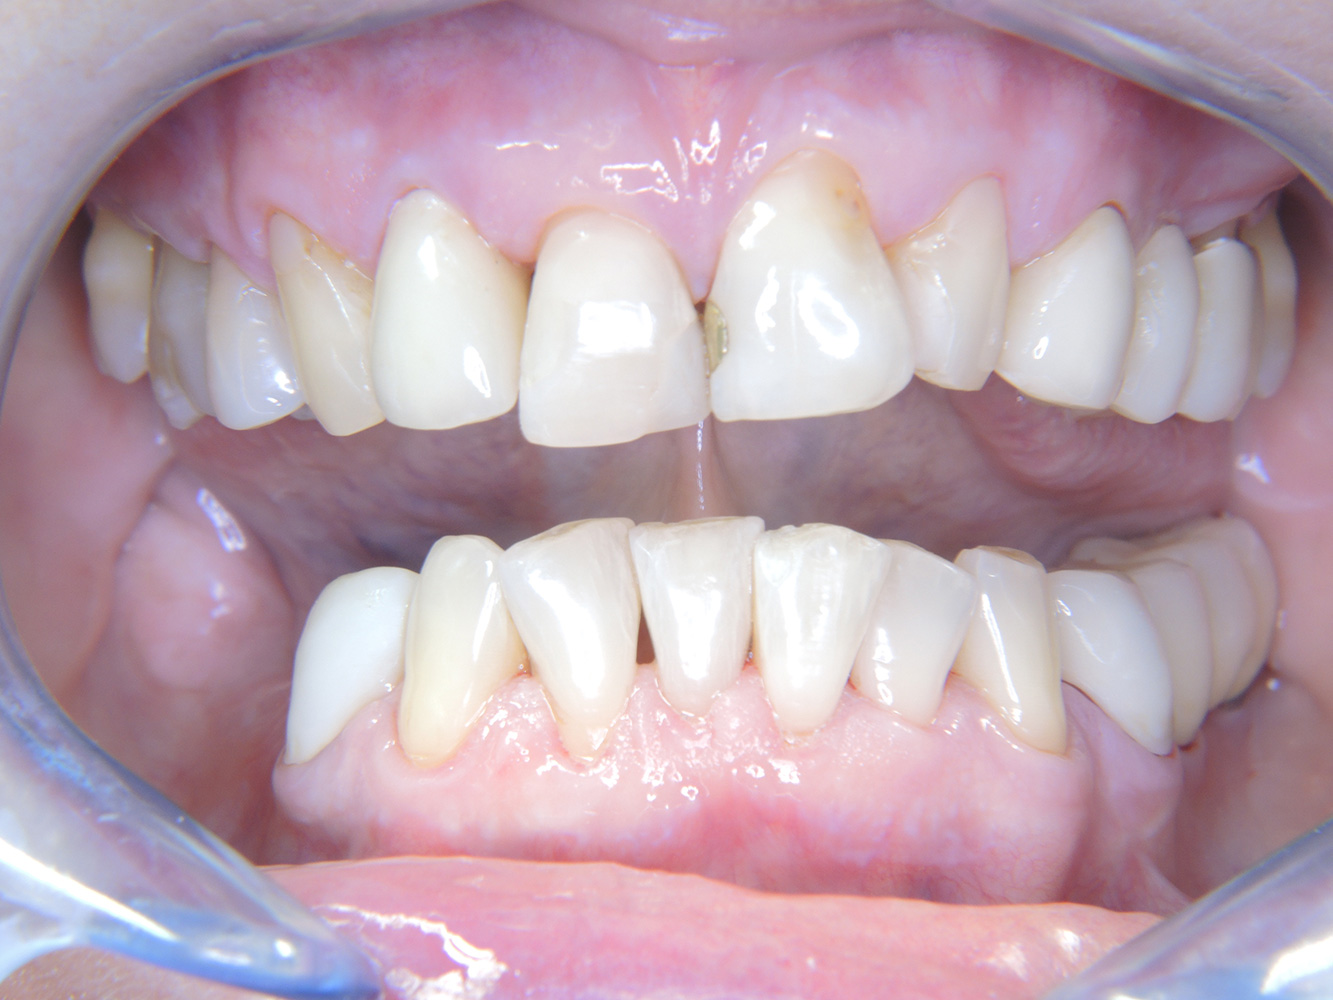

La paciente de 68 años no tiene enfermedades previas relevantes de la salud general ni toma medicación; sus hábitos alimentarios tampoco suponen un riesgo especial. La paciente tiene dos implantes (tercer cuadrante, desde hace cinco años) y una enfermedad previa periodontal (periodontitis en etapa IV, grado B) con pérdida dental. Actualmente las condiciones periodontales son estables, pero la periodontitis aumenta de manera determinante las complicaciones biológicas cuando se realizan implantes y puede ocasionar la pérdida de un implante (21). Para la sesión de profilaxis se hacen cuatro recomendaciones.

Dado que la paciente no tiene factores de riesgo especiales con efectos específicos para los dientes, las necesidades determinadas a partir de la salud oral son determinantes. Se recomienda un estado periodontal detallado una vez al año. De esta forma, es posible responder a la posible progresión de la enfermedad periodontal previa o al desarrollo de periimplantitis a tiempo.

Aunque las condiciones sean estables, no debe descuidarse la motivación y la formación de esta paciente. Hay que prestar especial atención a que aprenda a cómo cuidar los implantes correctamente. Aquí en particular, un buen mantenimiento en casa puede jugar un papel importante en la estabilización a largo plazo de la salud oral y del implante.